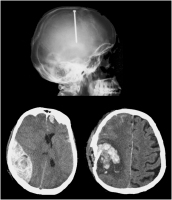

Nagelschussverletzung

Abbildung 1: Nagelschussverletzung, Epiduralhämatom und Impressionsfraktur mit Kontusionsblutung